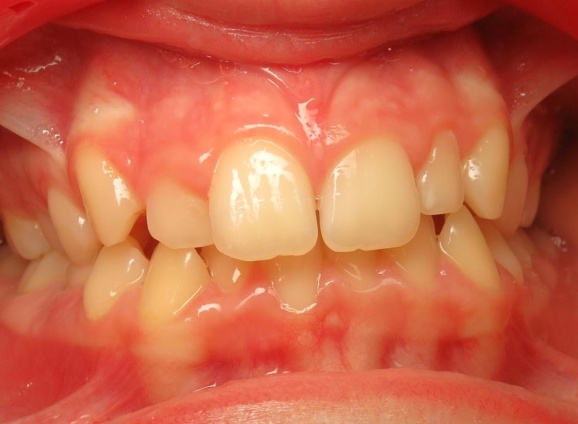

1 - Avant et après traitement

Un traitement orthopédique a permis d’optimiser la croissance des bases osseuses, offrant des conditions favorables à l’évolution de la dentition. Le traitement multiattaches a ensuite aligné les dents sur des structures squelettiques correctement développées.